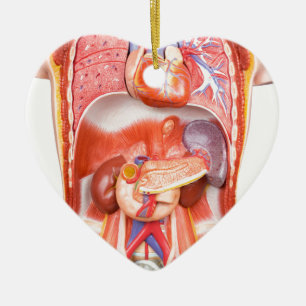

Kroppsmodell hos människa med organ vykort

Pris21,00 kr

Kroppsmodell hos människa med organ anteckningsblock

Pris150,00 kr

Kroppsmodell hos människa med organ vykort

Pris21,00 kr